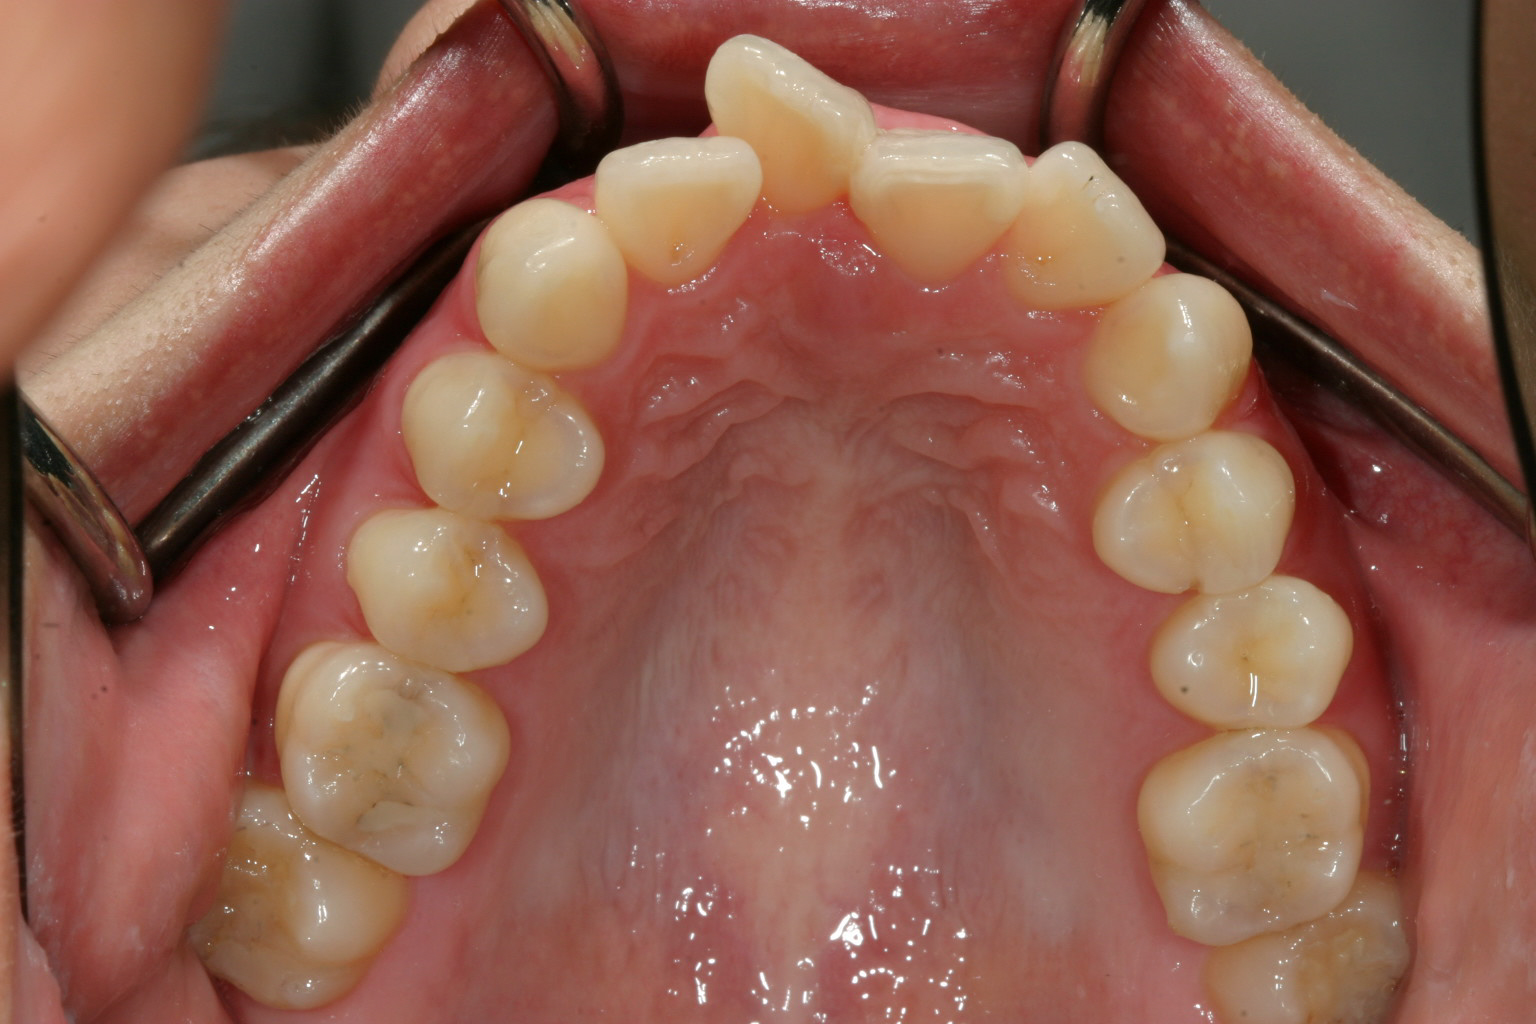

アーチがV字形の為前歯が並ばず前歯が翼状捻転しています。

今回のケースはアーチが狭窄(狭くなる)している為に前歯が並ばず翼状捻転し結果として前に飛び出していました。